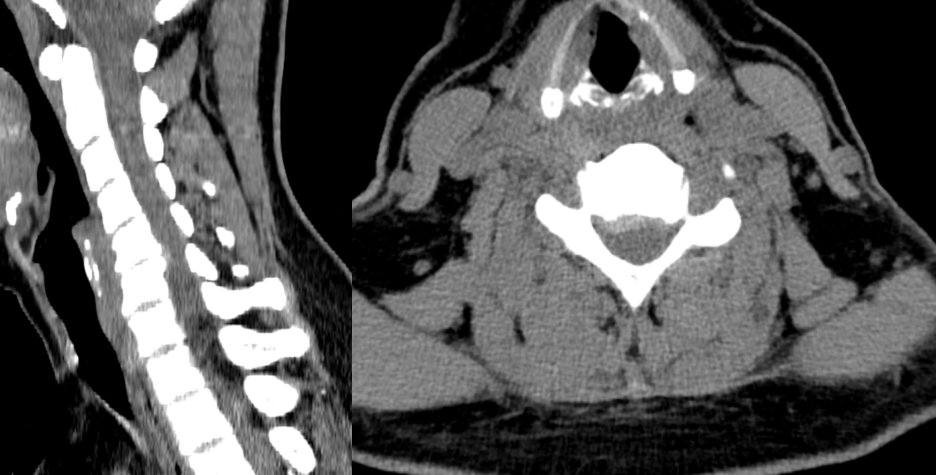

CT检查